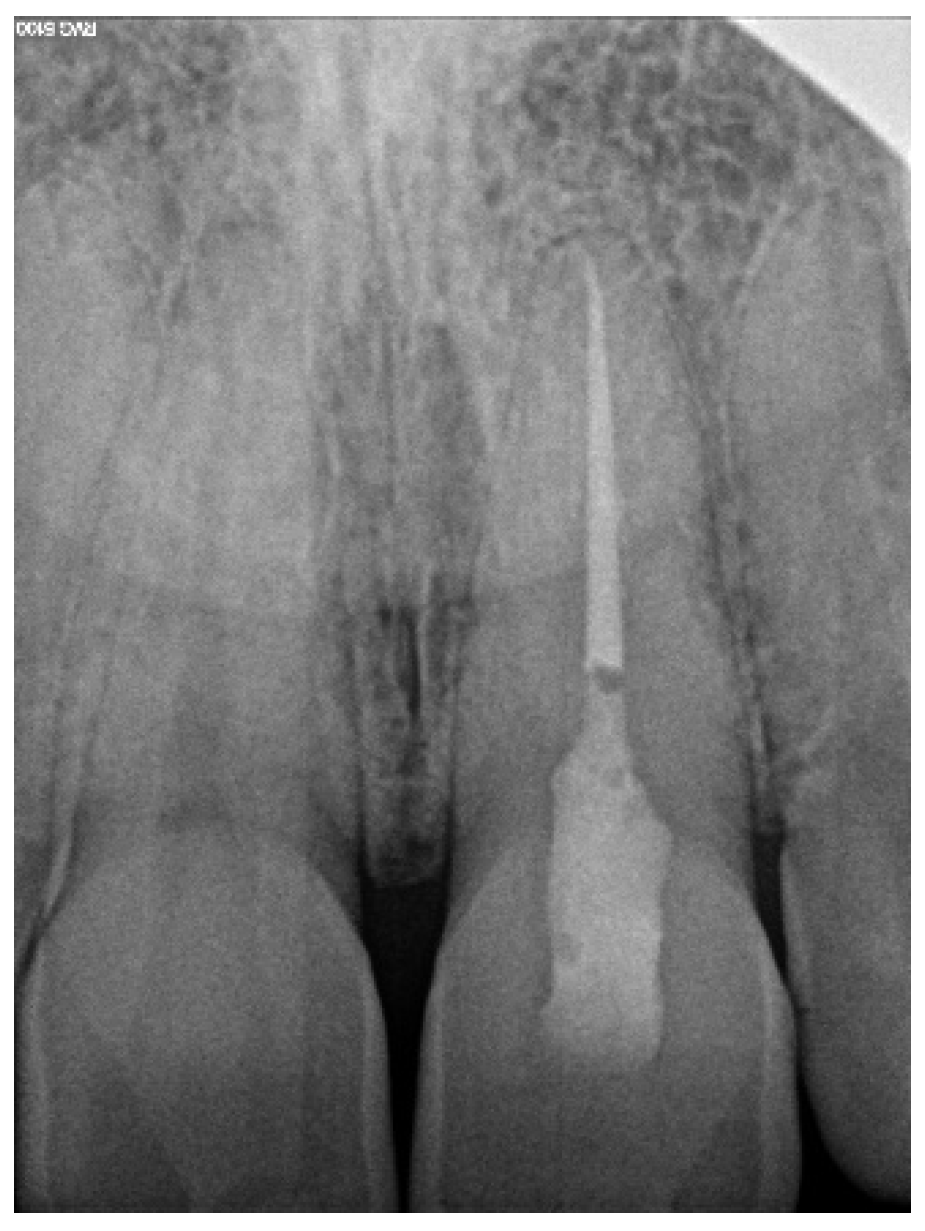

The correct fit of the guide was verified before and after the rubber dam was placed. For local anaesthesia, 1.7 mL Ubistesin forte (3 M ESPE, Seefeld, Germany) was administered (articaini hydrochloridum 40 mg + epinephrine hydrochloridum 0.012/1 mL). A small sign was made on the enamel surface through the guide to indicate the access point. The enamel was removed in a minimally invasive manner with a diamond bur until the dentine was exposed. The guide was placed on the teeth and the treatment was performed with Munce Discovery Bur #1 (CJM Engineering, Santa Barbara, CA, USA) with a speed of 10,000 rpm. This bur was a round carbide bur with a head diameter of 0.8 mm (ISO head size 08) and a total length of between 31 and 34 mm. The guide was removed every 2 mm to rinse the cavity, control endodontic access using an optical microscope, and clean the bur. After the bur reached the estimated depth, the C-Pilot #10 and #15 files (VDW, Munich, Germany) were used to check the canal position. Radiographic examination was performed to confirm correct canal access (Figure 15). The canal was reached at a length of 22 mm from the top of the guide sleeve - 1 mm deeper than the virtually planned depth. Once the remaining canal was reached, the length was confirmed with an electronic apex locator (Raypex 6; VDW, Munich, Germany). A conventional root canal treatment followed. The canal was irrigated with 5.25% sodium hypochlorite (NaOCl), including passive ultrasonic activation, and instrumented with ProTaper Gold (Dentsply Sirona Endodontics, Ballaigues, Switzerland) up to the F3 file size (0.30/0.09v). It was dried with paper points and obturated with vertically condensed gutta-percha and epoxy sealer (AH Plus, De Trey, Konstanz, Germany). The access cavity was cleaned and filled with a composite resin (Estelite Asteria, Tokuyama Dental Corporation, Tokyo, Japan).

Figure 15. Radiographic examination was used to confirm (a) correct path of access pathway during procedure and (b) correct root canal access; (c) post-obturation radiograph.